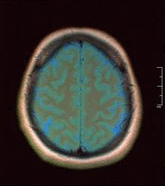

Einzelbild einer Magnetresonanz- tomographie eines menschlichen Gehirns -

Je nach Gewichtung kommen die verschiedenen Gewebe in charakteristischer Intensitätsverteilung zur Darstellung:

- In der T1-Gewichtung erscheint Fettgewebe hyperintens (signalreich, hell) und damit auch fetthaltige/-reiche Gewebe (z. B. Knochenmark). Diese Gewichtung eignet sich daher gut zur anatomischen Darstellung von Organstrukturen und insbesondere nach Kontrastmittelgabe (Gadolinium) zur besseren Abgrenzbarkeit unbekannter Strukturen (z. B. Tumor).

- In der T2-Gewichtung erscheinen stationäre Flüssigkeiten hyperintens, so dass flüssigkeitsgefüllte Strukturen (z. B. Liquorräume) signalreich und damit hell erscheinen. Dadurch eignet sich diese Gewichtung zur Darstellung von Ergussbildungen und Ödemen sowie z. B. zur Abgrenzung von Zysten gegenüber soliden Tumoren. Bei Röntgenbildern, insbesondere bei der speziellen Röntgentechnik der Computertomographie (CT), werden im Gegensatz dazu die Begriffe hyperdens und hypodens zur Beschreibung des relativen Schwärzungsgrads benutzt.

- Protonengewichtete Bilder sind flau, aber scharf. Knorpel kann sehr detailliert beurteilt werden. In Verbindung mit einem Fettsättigungsimpuls gehören PD-Bilder deshalb zum Standard in Gelenkuntersuchungen.